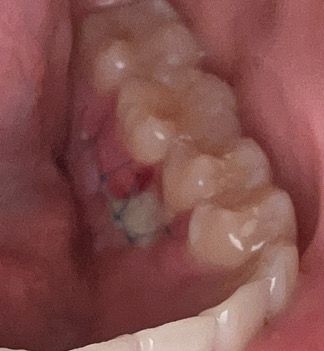

제가 혀쪽 아랫니 과잉치 발치를 하고 뼈 이식까지 한지 4일차정도가 됐는데요 아직까지 통증이 좀 있어요 그리고 쫌 한쪽이 벗겨진듯이 빨게요 괜찮을까요?

사진상으로 보면 잇몸이 잘 아물고 잇는거 같습니다. 자극이 가지 않도록만 주의 하시면될것같습니다.

치유과정에서 염증반응과 혈류가 잘 안통하는 부분은 괴사가 진행되고 있는 것 같은데요. 아직 4일차 이시니 통증도 있을 수 있고 너무 걱정마시고 경과를 조금 지켜보시면 되겠습니다.

치아를 발치한 부위가 아물기 위해서는 2주정도의 시간이 걸립니다. 사진을 봤을경우에는 크게 문제가 없이 아물고 있는것으로 보입니다.

사진으로 봐서는 특별히 이상한 점은 없어 보입니다. 통증은 미약하게라도 1주일까지 지속되기도 합니다.

이정도면 정상적으로 아물고 있는 것입니다. 부분적으로 빨갛게 보이는 것은 그 부위가 다른 부위 보다 아무는 속도가 늦기 때문이며 이런 사소한 것은 문제되지 않습니다.